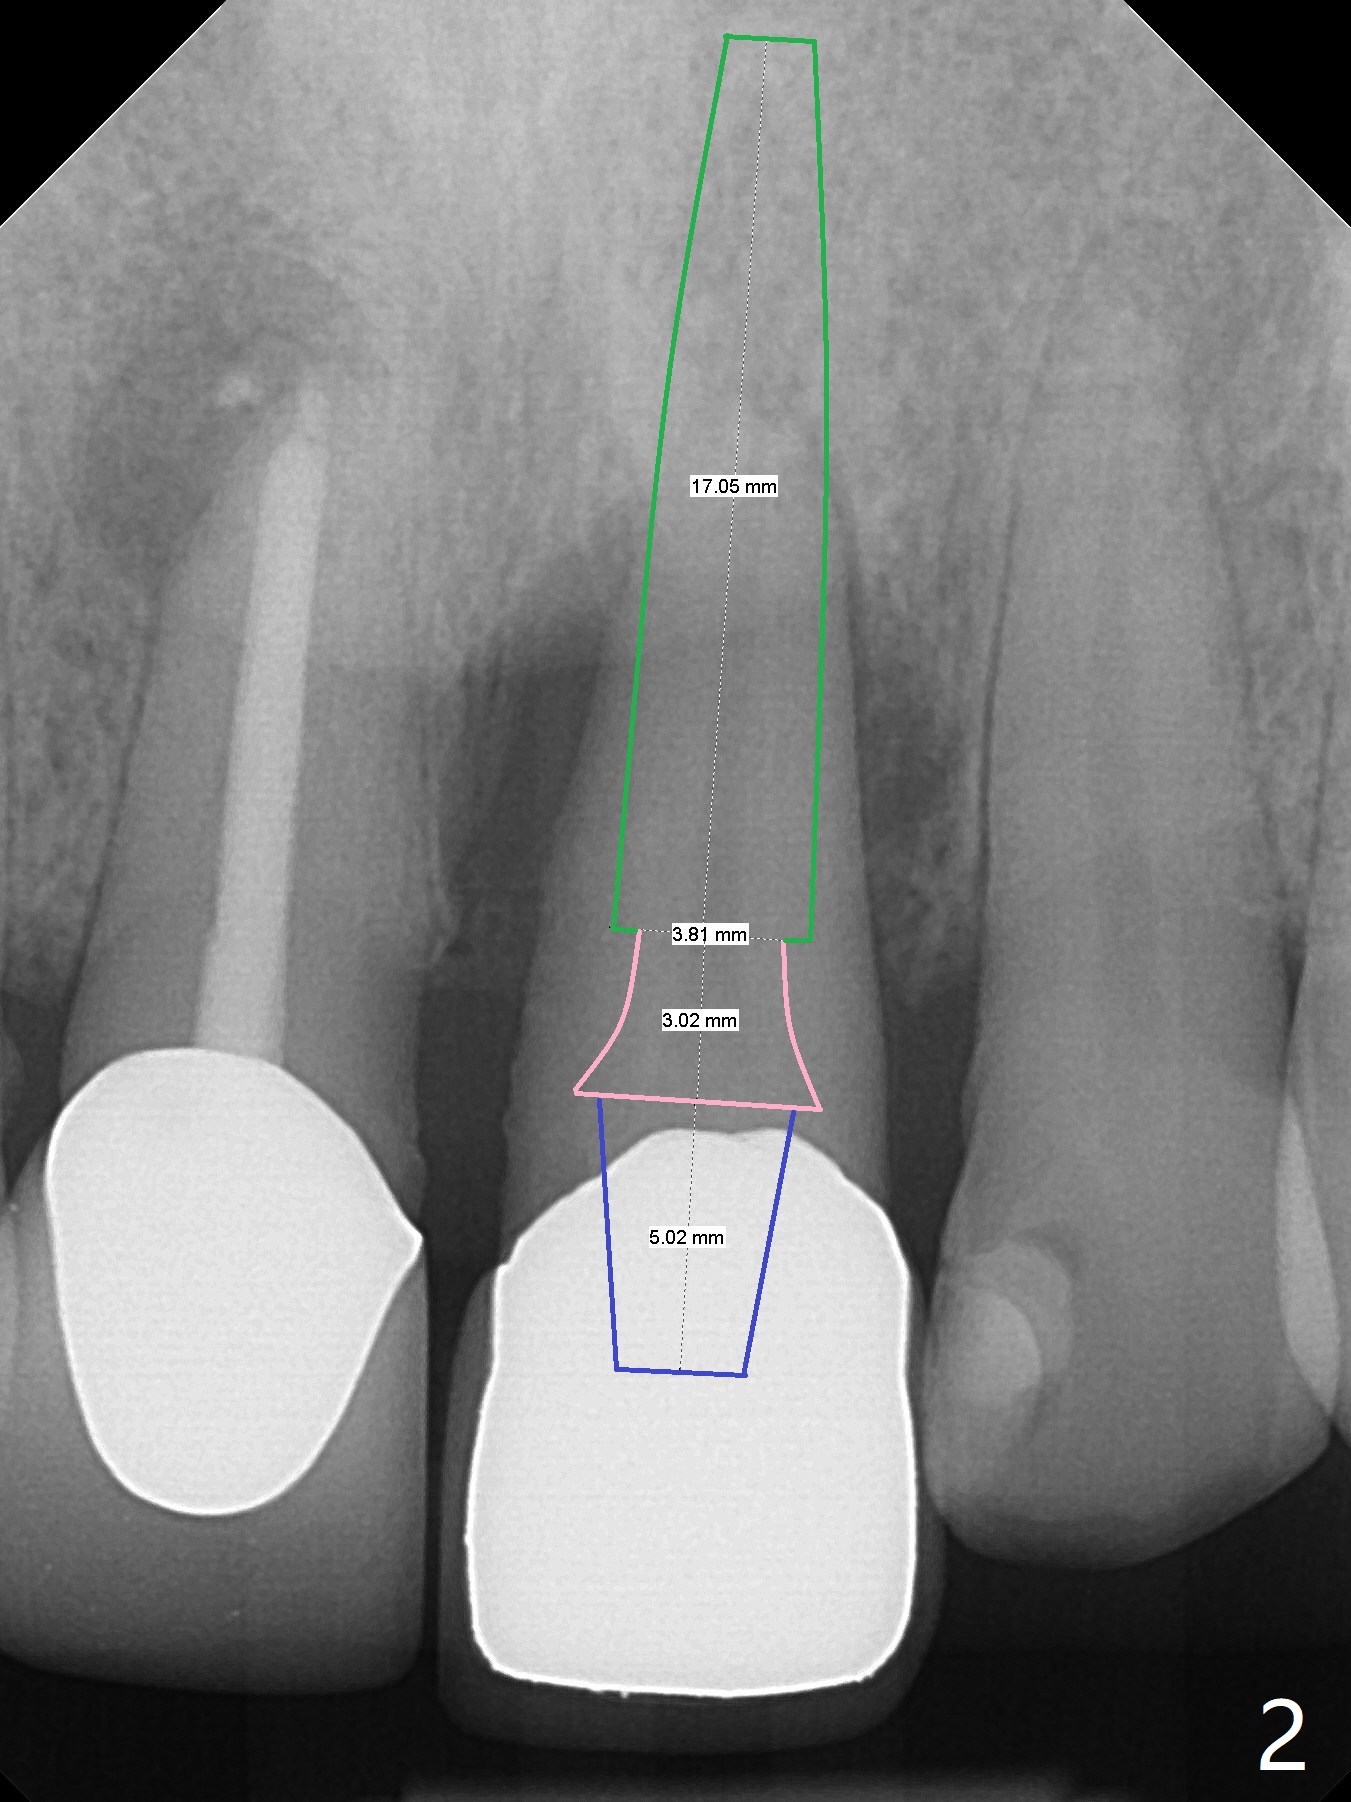

A 54-year-old man appears to be a unilateral masticator because of missing #30 (Fig.1). The left central incisor seems to have root fracture (Fig.2). To counter heavy occlusal force, a long implant will be placed (Fig.2,3).